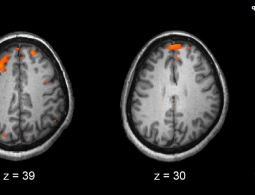

Мозг: переосмыслить, чтобы понять

Понять человеческий мозг — бесспорно, это одна из сложнейших задач современной науки. Ведущий подход на протяжении большей части последних 200 лет заключался в том, чтобы связать функции мозга с различными его областями или даже отдельными нейронами (клетками головного мозга). Но последние исс...